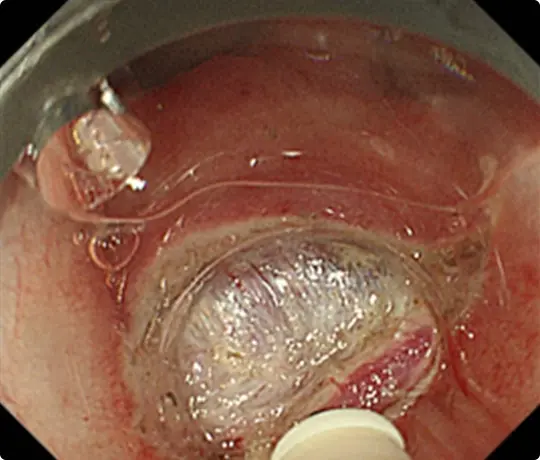

約3cmの大きな大腸ポリープです。

スネアでポリープの根元を縛り、電流を流して切除します(出血予防のためポリープの根元にクリップをうっています)。

切除した検体です。病理検査で早期大腸がんと診断されました。がんは完全に切除されており、治癒と判定されました。